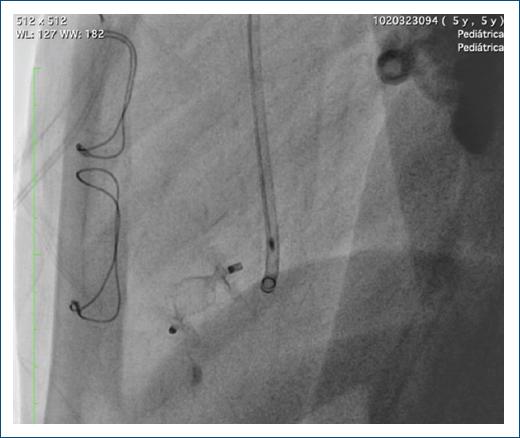

Se pasó un introductor Flexor 6 Fr hasta el ventrículo izquierdo, luego se avanzó al catéter non taper distal en el divertículo y se pasó un guía de soporte Amplatz 0.035, sobre la cual se pasó un catéter guía JR 6 Fr. Se avanzó un AVP II de 10 mm, liberando el extremo distal y el tambor central en la cavidad del divertículo y en la boca distal, y por último se liberó el disco proximal (Fig. 7). Se realizó una maniobra de Minessotta wiggle para evaluar la estabilidad del dispositivo, que permaneció estable, y finalmente se liberó (Fig. 8). La angiografía de control mostró el dispositivo en posición con oclusión del divertículo (Fig. 9).

El procedimiento se realizó con ecocardiografía transesofágica y transtorácica en forma simultánea, demostrando en la imagen final la desaparición del flujo dentro del divertículo. Se observó la bolsa pericárdica apical izquierda sin cortocircuito residual. En la punta del ventrículo izquierdo se observó una bolsa pericárdica residual ocluida completamente por el dispositivo Amplatzer Vascular Plug II de 10 mm, con función ventricular sistólica conservada y excursión sistólica del anillo tricúspide de 21 mm (Fig. 10).